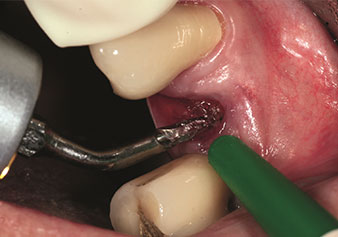

Situation following piezosurgical extraction

Fig. 2: Situation following piezosurgical extraction. Photo: © Dr Torsten Conrad (Bingen am Rhein)

One application, which is often underestimated is the atraumatic extraction of tooth roots or root fragments in the scope of alveolar management. The fine periotomes, which are currently available in two versions (EX1 and EX2 from W&H), can also be used to remove teeth which have previously undergone special endodontic treatment or ankylosed roots with ease. This results in extraction alveoli where both the hard and soft tissue are fully intact as it is generally possible to avoid reflection.

This establishes the optimal basis for subsequent or immediate implant treatment (Figures 1 and 2 included with the kind permission of Dr Torsten Conrad, Bingen a. Rhein).